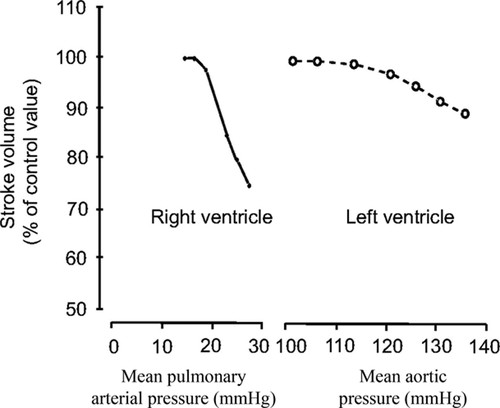

Các yếu tố quyết định chức năng TP bao gồm lưu lượng đổ về từ tĩnh mạch chủ, áp lực ĐMP (hậu gánh), sự giới hạn của màng ngoài tim, khả năng co bóp của thành tự do TP và vách liên thất. Trong các yếu tố này, hậu gánh là yếu tố chính đảm bảo chức năng bình thường của TP. Phân suất tống máu thất phải (RVEF) tỷ lệ nghịch với áp lực động mạch phổi. Một thay đổi nhỏ về áp lực cuối tâm thu thất phải đã tạo ra sự thay đổi lớn về thể tích cuối tâm thu thất phải. Do vậy chức năng tâm thu TP rất nhạy cảm với những thay đổi về hậu gánh, chỉ với sự gia tăng nhỏ về hậu gánh cũng đã gây ra giảm thể tích tống máu TP (Hình 4)

Hình 4.Thay đổi thể tích tống máu của thất phải (RV) và thất trái (LV) khi tăng hậu gánh (qua thực nghiệm). Cùng một mức tăng về áp lực, thể tích tống máu (stoke volum-SV) thất trái giảm rất ít, trong khi đó thể tích tống máu (SV) thất phải giảm nhiều. Nguồn MacNee W. Am J respir Crit Care Med. 1994; 150: 883 - 52.20.